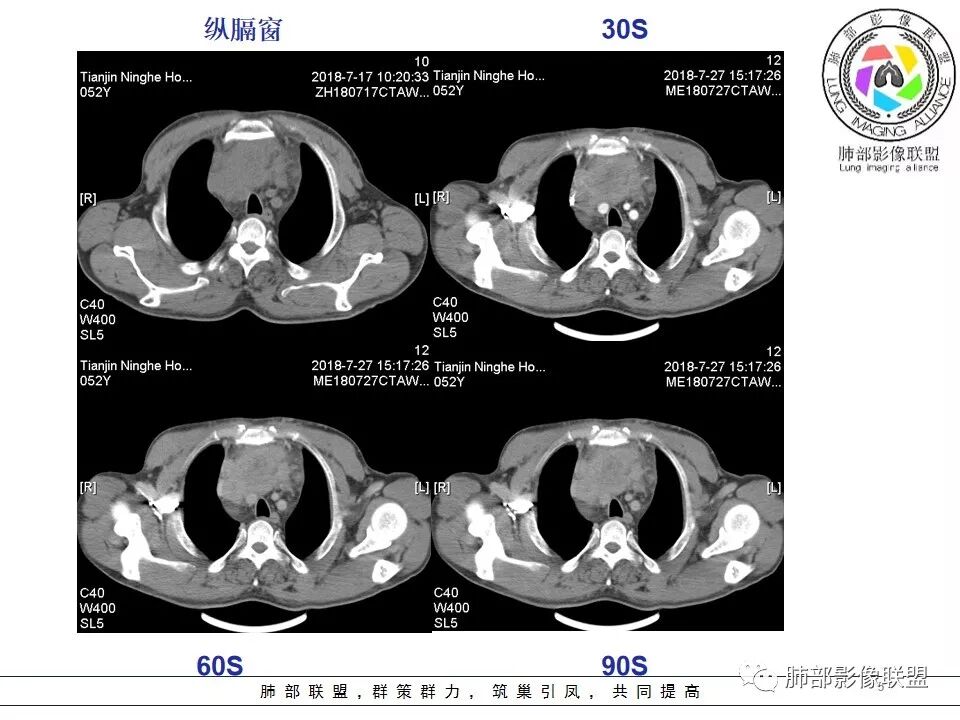

Yiren  Sishui(厶水伊人):上腔静脉受压后移,无侵犯,内乳动脉在其外侧,中心生长,定位纵隔,年龄>30岁,浅分叶,未见明显纤维分隔,其内见微钙化,坏死明显,周围脂肪间隙模糊,心包受累,考虑B3型胸腺瘤或胸腺癌.

采莲:中年男性,前纵隔巨大肿块,基本居于中央,上腔静脉受压变窄,内有大片坏死,肿块内及周围有更低密度囊性影,考虑恶性胸腺瘤?鉴别淋巴瘤。

崔少钢:中年男性,左侧颈内静脉、左侧前胸壁及左上臂静脉曲张,提示有静脉阻塞,另患者有恶性家族史。影像:前纵隔占位,有浅分叶,周围脂肪间隙不清晰,且见小淋巴结,内有坏死,上腔静脉受侵,内有钙化,支持胸腺癌。

上腔静脉如何?

大肿块,边缘不清,伴随肿大淋巴结,上腔静脉受侵犯——恶性

4.  纵隔淋巴结肿大及纵隔大血管(上腔静脉)受侵犯,提示胸腺癌或类癌。